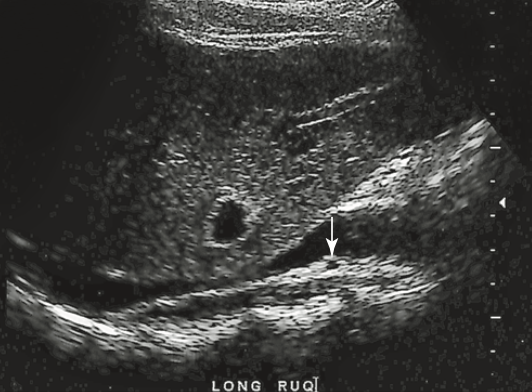

a patient presents to the emerg with a history of severe epigastric pain. Lab results are pending. An abdominal US is ordered to rule out biliary disease. Which pathology is identified here

choledocholithiasis